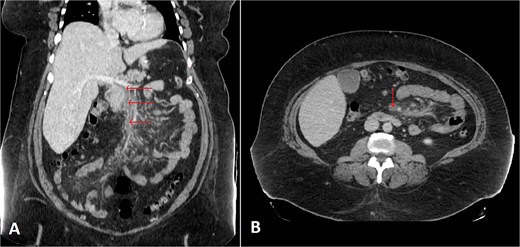

A contrast-enhanced abdominal and chest CT scan (Fig. 1) revealed an intra-luminal filling defect in the superior mesenteric vein (SMV), extending proximally to the main portal vein, associated with mesenteric fat haziness along the SMV and its tributaries. These findings were consistent with portomesenteric venous thrombosis (PMVT). The patient was admitted to the medical ward, kept NPO (nothing by mouth), and further blood tests were ordered. The results revealed the patient to be heterozygous for factor V Leiden, with low levels of antithrombin III, a beta-fibrinogen mutation (455G>A), and the MTHFR C677T gene mutation.

Selected coronal (A) and axial (B) cuts of the patient’s abdomen CT scan with IV contrast showing intra-luminal filling defect in the SMV, extending proximally to the proximal part of the main portal vein (arrows) associated with surrounding mesenteric fat haziness, representing portomesenteric venous thrombosis.